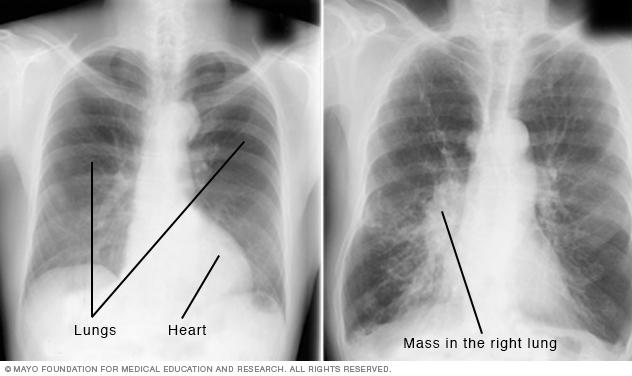

Medical image of chest X-rays

Chest X-ray

A chest X-ray helps detect problems with the heart and lungs. The chest X-ray on the left is typical. The image on the right shows a mass in the right lung.

• Lung infections or conditions. Evidence of pneumonia, tuberculosis or lung cancer can show up on chest X-rays.